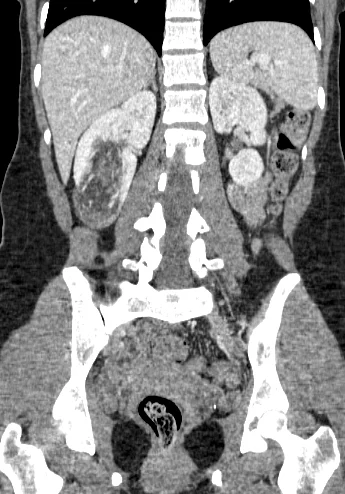

Visceral Embolization: Case 6

32 year old female who presents with an incidentally discovered right renal angiomyolipoma and undergoes prophylactic embolization.

Comment: This case demonstrates the classic appearance of an angiomyolipoma on CT and the hypervascularity associated with this benign tumor. The clearly seen abnormal vasculature enabled selective catheterization of the dominant supply to the angiomyolipoma and subsequent selective embolization with PVA particles. Embolization can be performed successfully with several types of particulate and/or liquid embolic agents. In this case, PVA was used successfully and no growth or viability has been seen on follow-up imaging after this procedure.